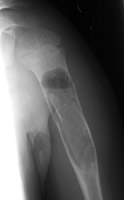

Diagnosis:Unicameral bone cyst Discussion:Two radiographs of a pathologic fracture in a simple bone cyst of the proximal humerus. Within the cyst is noted a small, thin, linear bony fragment which is displaced from the site of the fracture. An excellent sign of unicameral bone cyst. The fallen fragment secondary to pathologic fracture is pathognomonic for this cyst. A portion of the wall of the cyst has undergone a pathological fracture and subsequently floated down (fallen) via gravity into the dependent portion of the cyst. References: